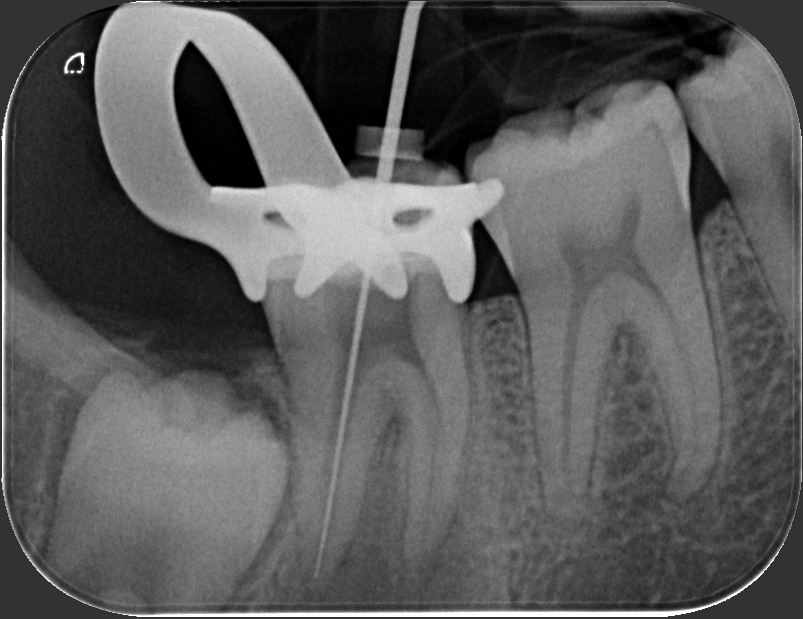

Caso clinico – trattamento ortogrado di 2° molare inferiore